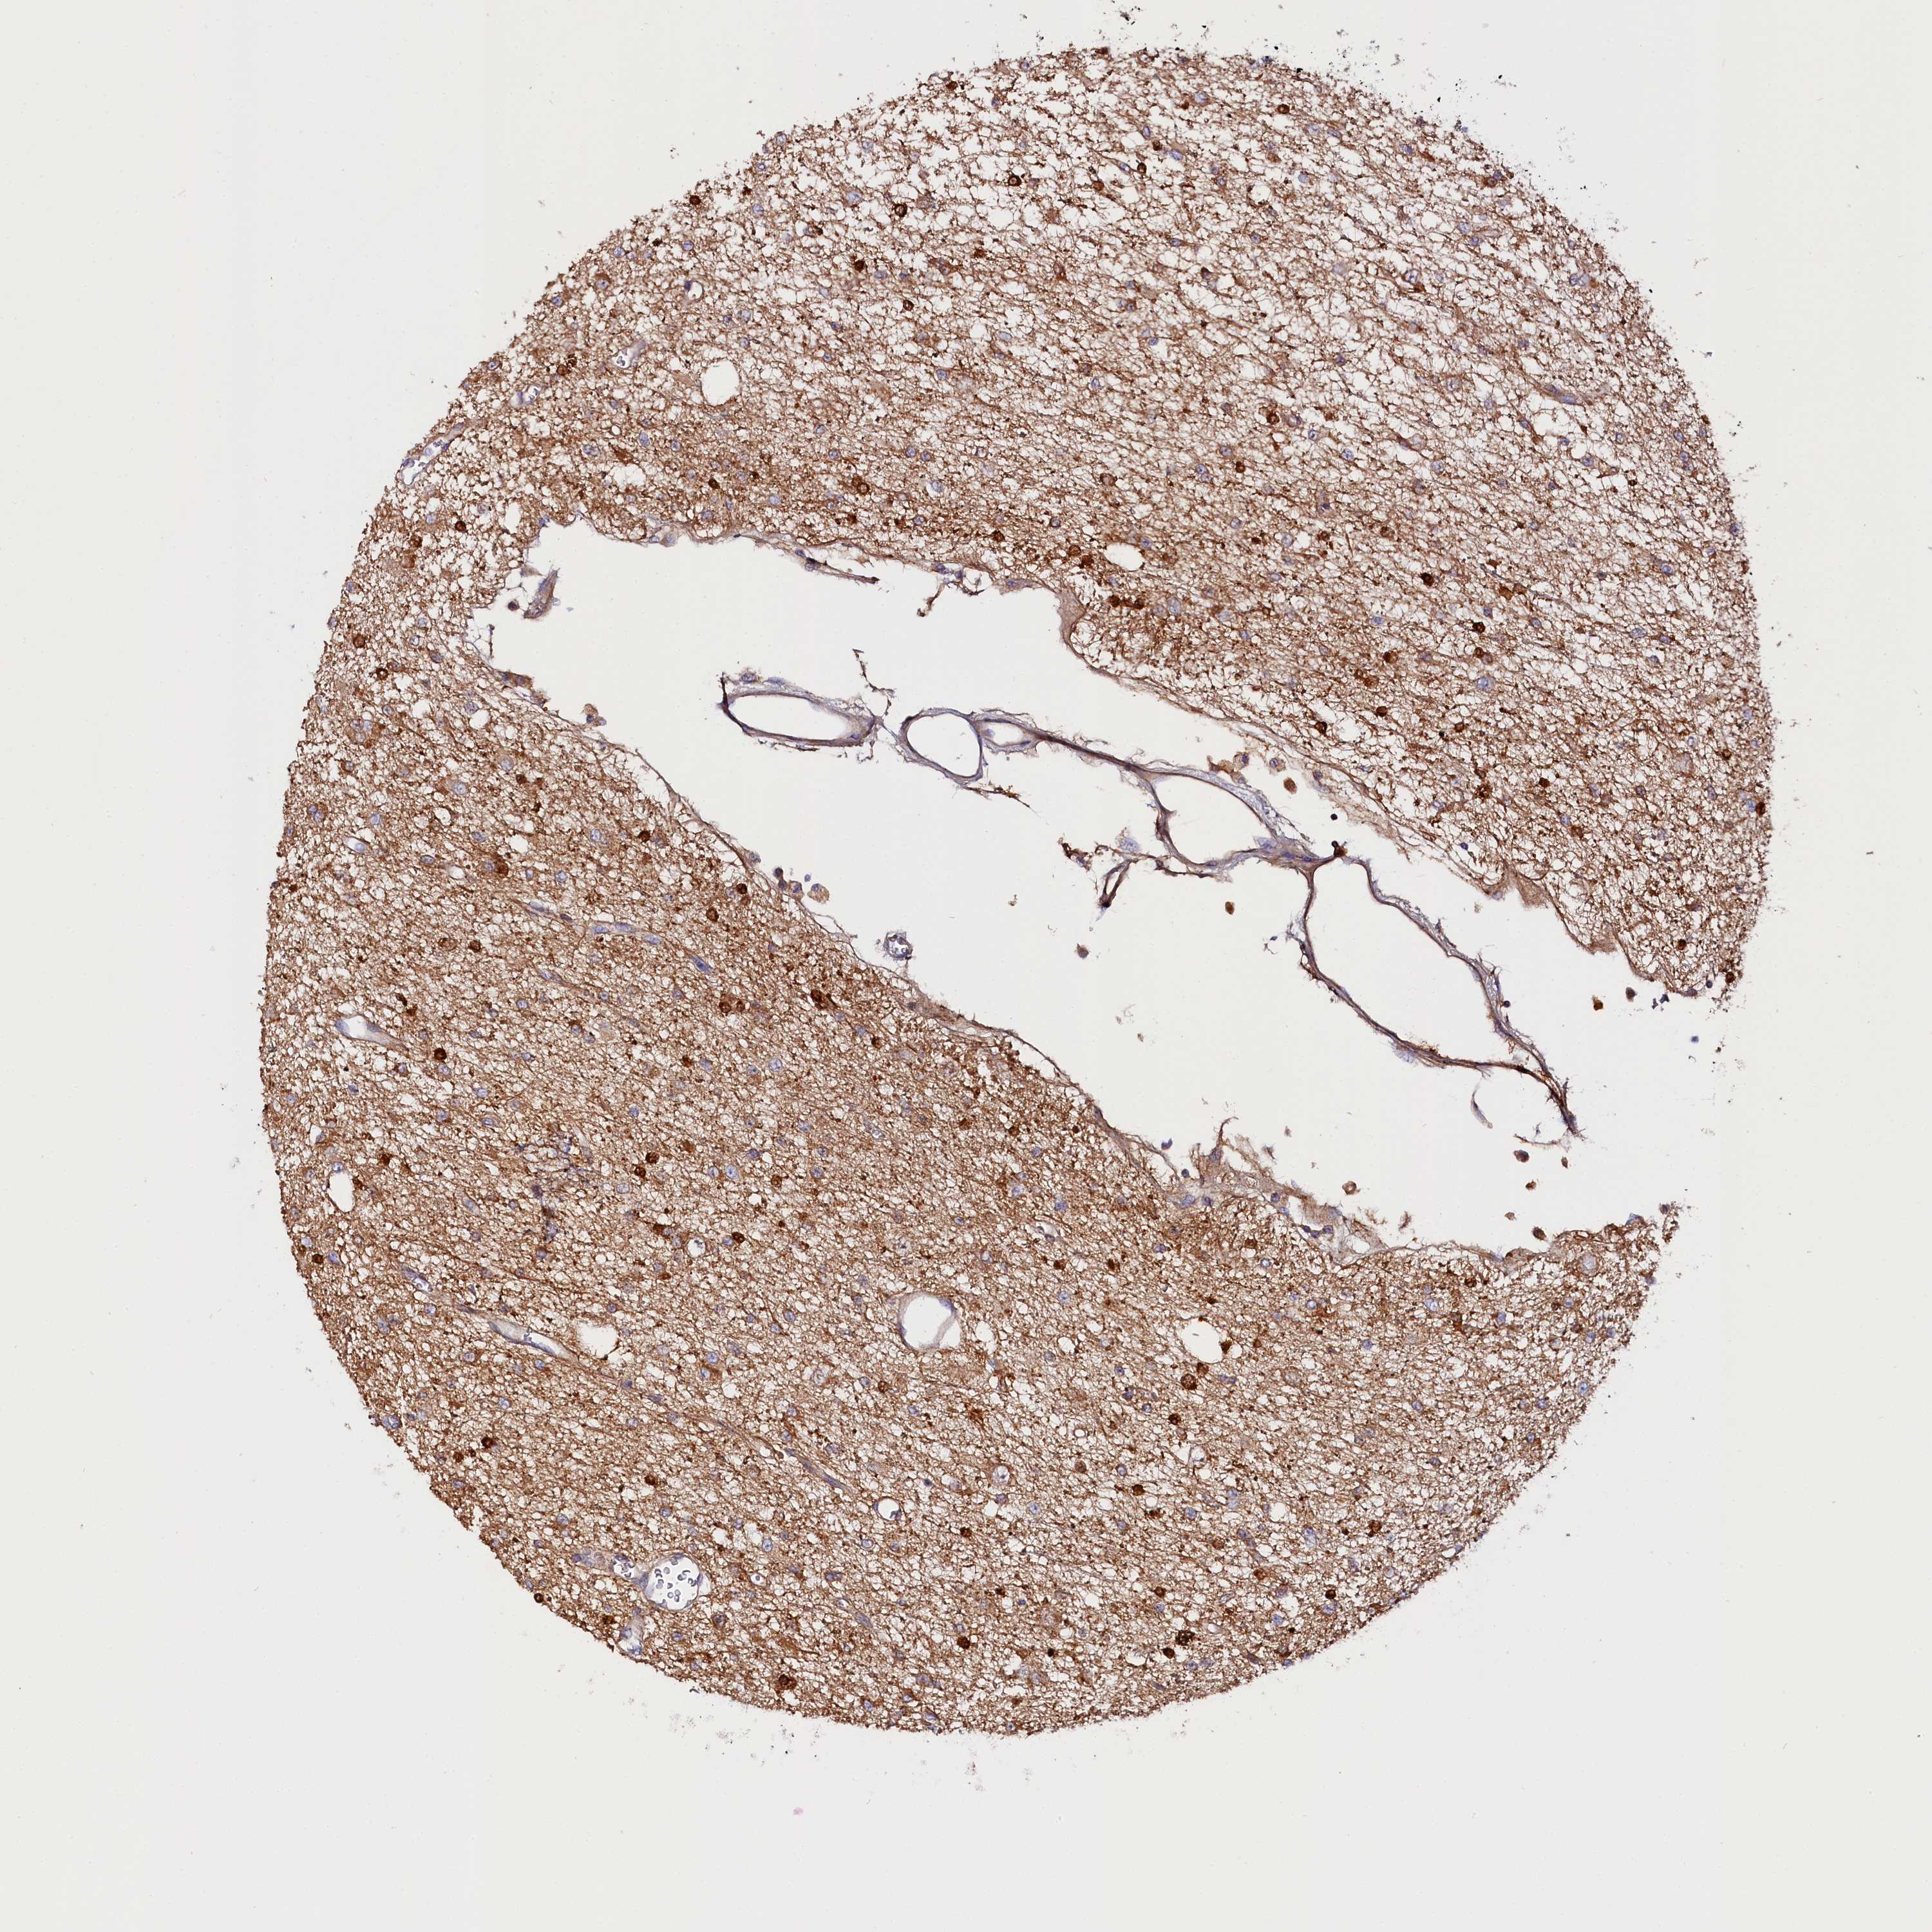

GLIOMA - Protein expressioni

A mouse-over function shows sample information and annotation data. Click on an image to view it in a full screen mode. Samples can be filtered based on level of antibody staining by selecting one or several of the following categories: high, medium, low and not detected. The assay and annotation is described here.

Note that samples used for immunohistochemistry by the Human Protein Atlas do not correspond to samples in the TCGA dataset.

Antibody stainingi

Antibody staining in the annotated cell types in the current human tissue is reported as not detected, low, medium, or high, based on conventional immunohistochemistry profiling in selected tissues. This score is based on the combination of the staining intensity and fraction of stained cells.

Each image is clickable and will lead to virtual microscopy that enables deeper exploration of all samples and also displays staining intensity scores, fraction scores and subcellular localization as well as patient and tissue information for each sample.

Antibody HPA041165

Antibody HPA041839

Staining

High

Medium

Low

Not detected

Intensity

Strong

Moderate

Weak

Negative

Quantity

>75%

75%-25%

<25%

None

Location

Nuclear

Cytoplasmic/membranous

Cytoplasmic/membranous,nuclear

Glioma, malignant, High grade

Glioma, malignant, Low grade